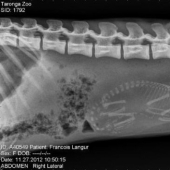

Who lives in the little house: X-rays of pregnant animals

Have you ever wondered what happens in the womb of a pregnant cat or dog? How do all these tiny babies fit in there and manage to ...